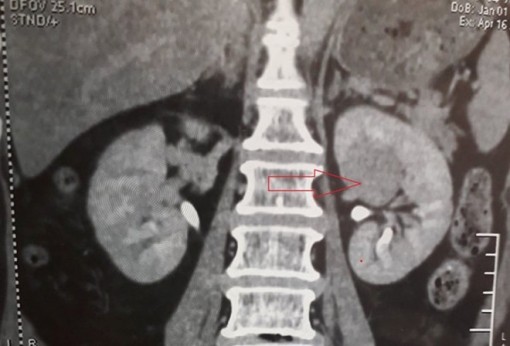

Một ca bị khối u ở trung tâm bể thận vừa được các bác sĩ ở Cần Thơ cấp cứu thành công bằng mổ nội soi sau phúc mạc cắt thận do khối u chưa di căn.